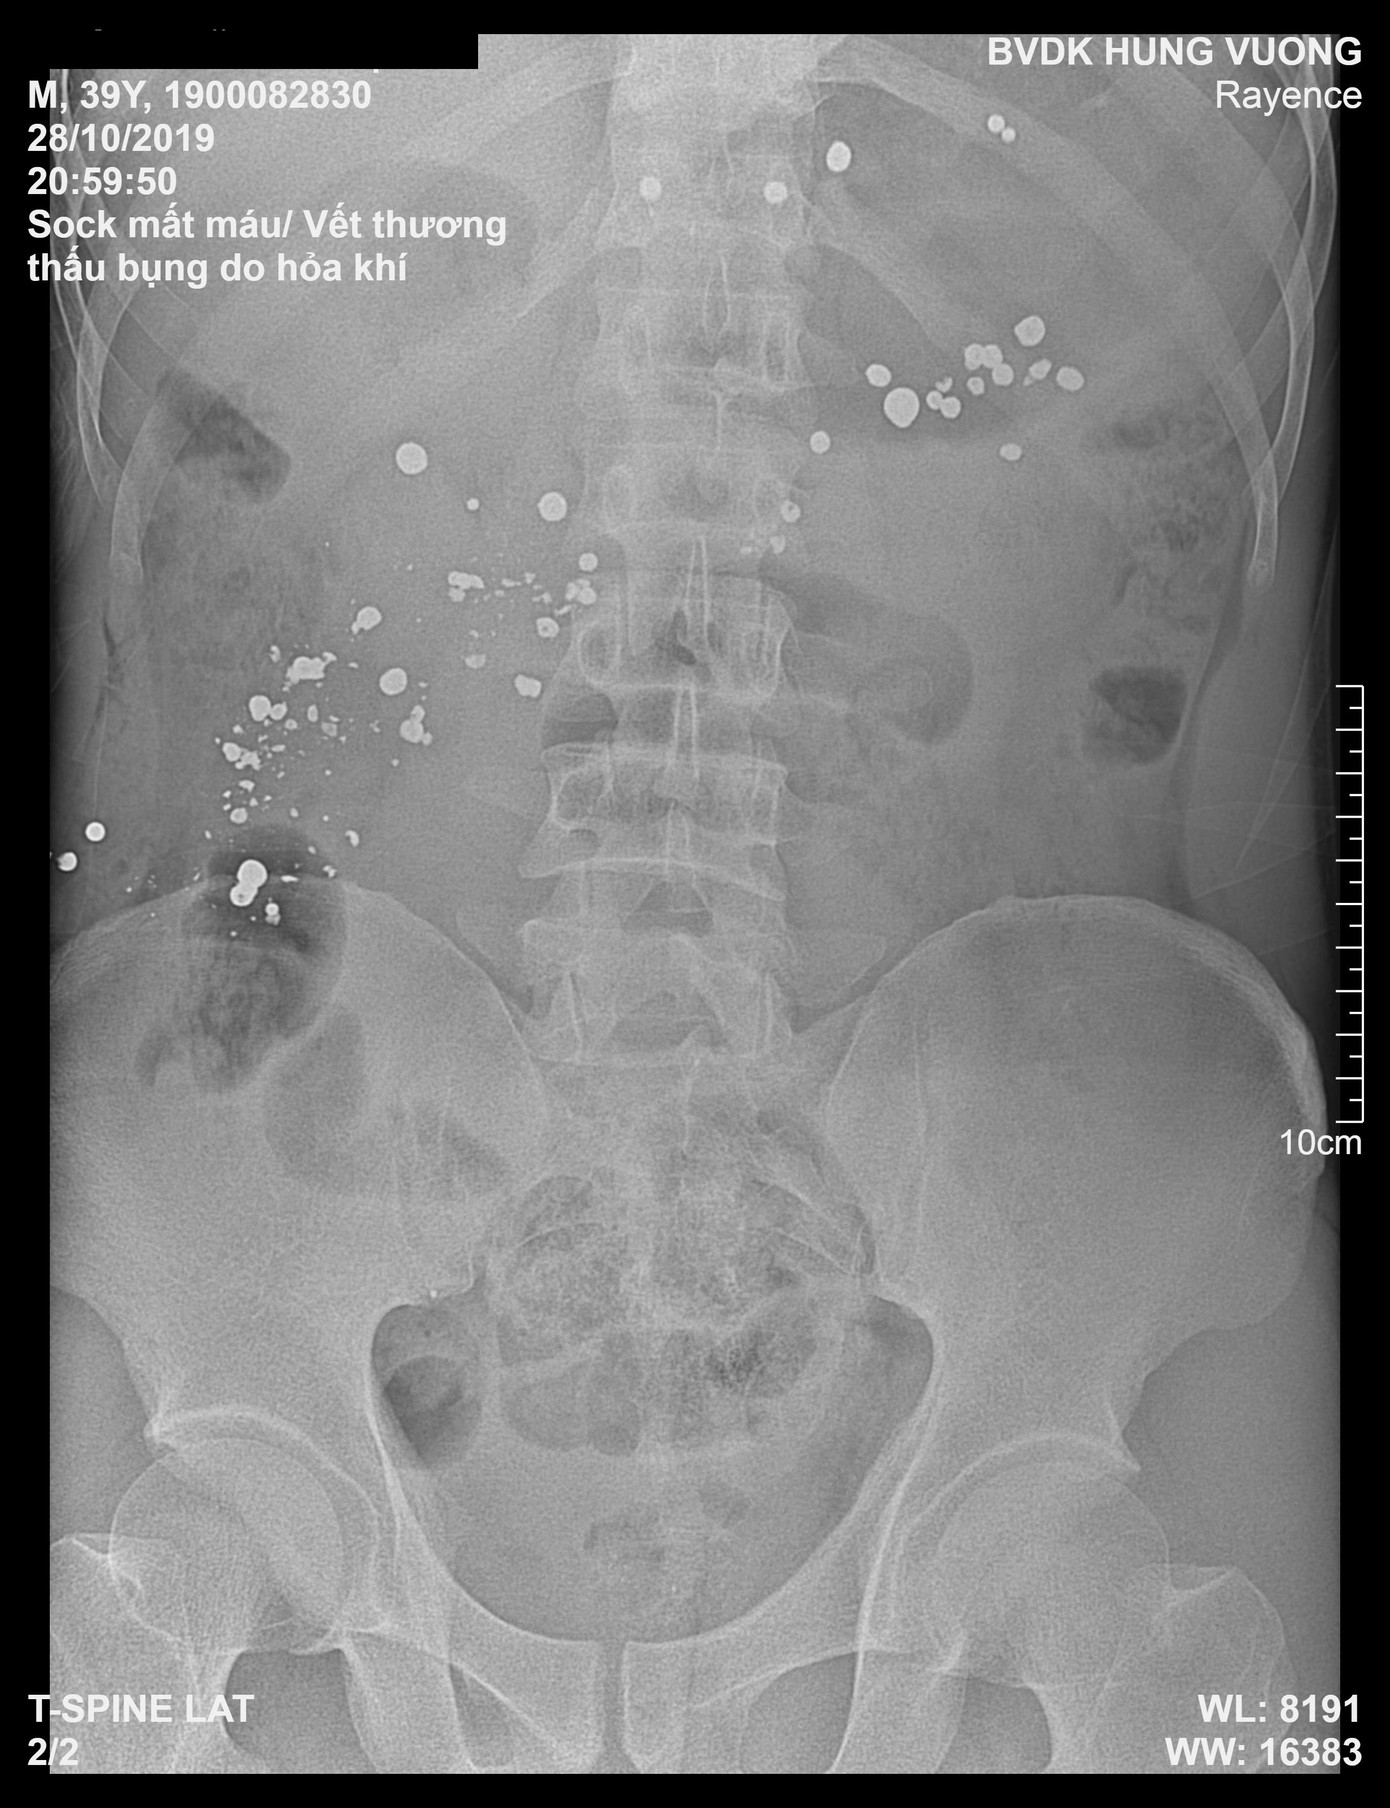

Qua hệ thống chụp X Quang và chụp cắt lớp, các bác sĩ chẩn đoán hình ảnh phát hiện có rất nhiều dị vật kim khí cản quang trong ổ bụng, mạn sườn trái và vùng khung chậu, và ra y lệnh mổ cấp cứu và truyền máu ngay lập tức. Trong quá trình thực hiện mổ cấp cứu, bệnh nhân đã được truyền 4 đơn vị máu.

Phim chụp Xquang cho thấy có nhiều dị vật kim khí trong ổ bụng bệnh nhân